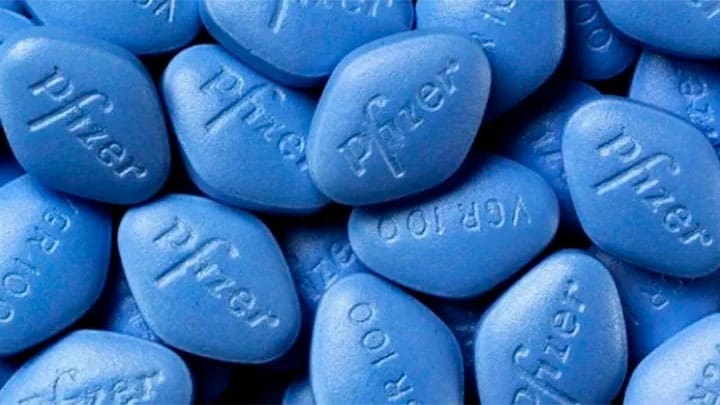

Toluca.- El Director General de Pfizer México, Rodrigo Puga, reconoció que el medicamento para la disfunción eréctil, mejor conocido como Viagra, es el producto que más...